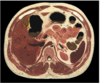

13

Q

labe lthe following

- liver

- gallbladder

- spleen

- pancreas

- kidney

A